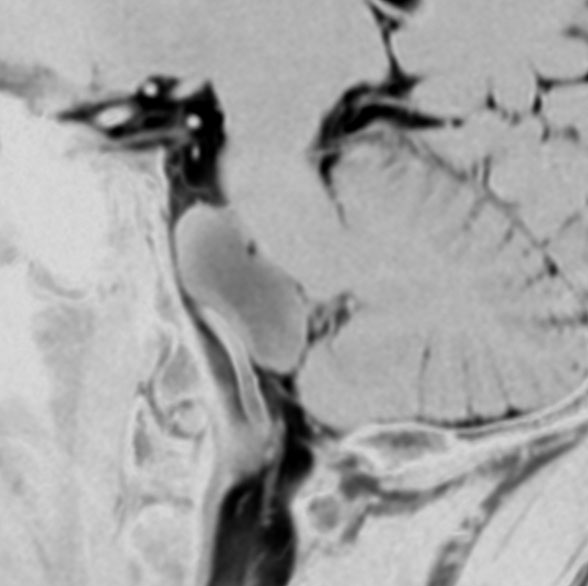

内胚葉のう胞,コロイドのう胞,ラトケのう胞ともいえる例

5歳の時に発見され23歳まで18年間経過観察をされてきた患者さんです。腫瘍はゆっくり,しかし確実に増大して,手術前には頭痛がひどく薬も効かず歩けなくなったという症状でした。術後に頭痛が無くなったので,のう胞による症状だったのでしょう。

下垂体柄の周囲にのう胞性腫瘍があります。T1強調画像では等信号,T2強調画像ではまだらな信号になっています。23年という長い経過から液状内容物が固形化したものと推定されます。T2で低信号となる部分があるのですが,黄色肉芽腫とは異なる像です。

下垂体柄は長く伸びています。のう胞による長期の圧迫のため斜台上部がerosionになって凹んでいます。トルコ鞍内の中間葉の位置に典型的な小さなラトケのう胞(黄色矢印)がみられますが,これは長年変化していませんでした。

左前頭側頭開頭 pterional approachで,のう胞壁を含めて完全摘出 complete removalしました。のう胞は下垂体柄の左側に付着してそこから発生したものでした。内容物は固体で寒天状のコロイドでした,一部軟らかくて一部は線維化していました。のう胞壁は半透明で薄い部分も線維性の膜状の部分もありました。病理検査では上皮細胞が証明されて内胚葉のう胞 endodermal cystの診断です。

ラトケのう胞はhiatusから内容液吸引だけして,皮膜はもちろんそのままにしています。